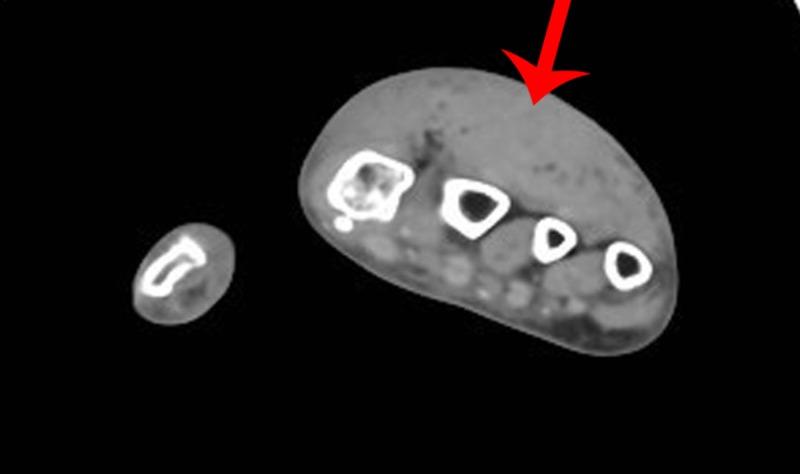

Acute compartment syndrome (ACS) of the hand is uncommon, especially secondary to exotic animal bites. In this case, we describe a patient who developed ACS of the hand after being bitten by her pet, an African grey parrot. The patient required emergent fasciotomy that resulted in symptom improvement. Furthermore, the patient developed an abscess leading to the consideration of antibiotic coverage for bird bites. This case provoked the consideration of compartment syndrome on the differential for minor crush or unusual injuries. It is also important to recognize that compartment syndrome may occur in any fascial compartment. As bird-related injuries are uncommon, we have briefly discussed antibiotic coverage for bird bites and associated zoonoses. We believe this is the first reported case of compartment syndrome of the hand from a parrot bite.

手部急性骨筋膜室综合征(ACS)并不常见,尤其是继发于外来动物咬伤时。在此病例中,我们描述了一名患者,她被自己的宠物——一只非洲灰鹦鹉咬伤后发生了手部急性骨筋膜室综合征。患者需要紧急进行筋膜切开术,术后症状有所改善。此外,患者还出现了脓肿,因此考虑针对鸟类咬伤使用抗生素。该病例促使我们在鉴别轻微挤压伤或特殊损伤时考虑骨筋膜室综合征。同样重要的是要认识到,骨筋膜室综合征可能发生在任何筋膜间隔。由于与鸟类相关的损伤并不常见,我们简要讨论了针对鸟类咬伤及相关人畜共患病的抗生素使用。我们认为这是首例因鹦鹉咬伤导致手部骨筋膜室综合征的报告病例。